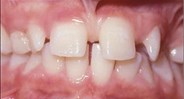

Photographs

side front front smile

Lateral Portrait Frontal Portrait Frontal Portrait Smile